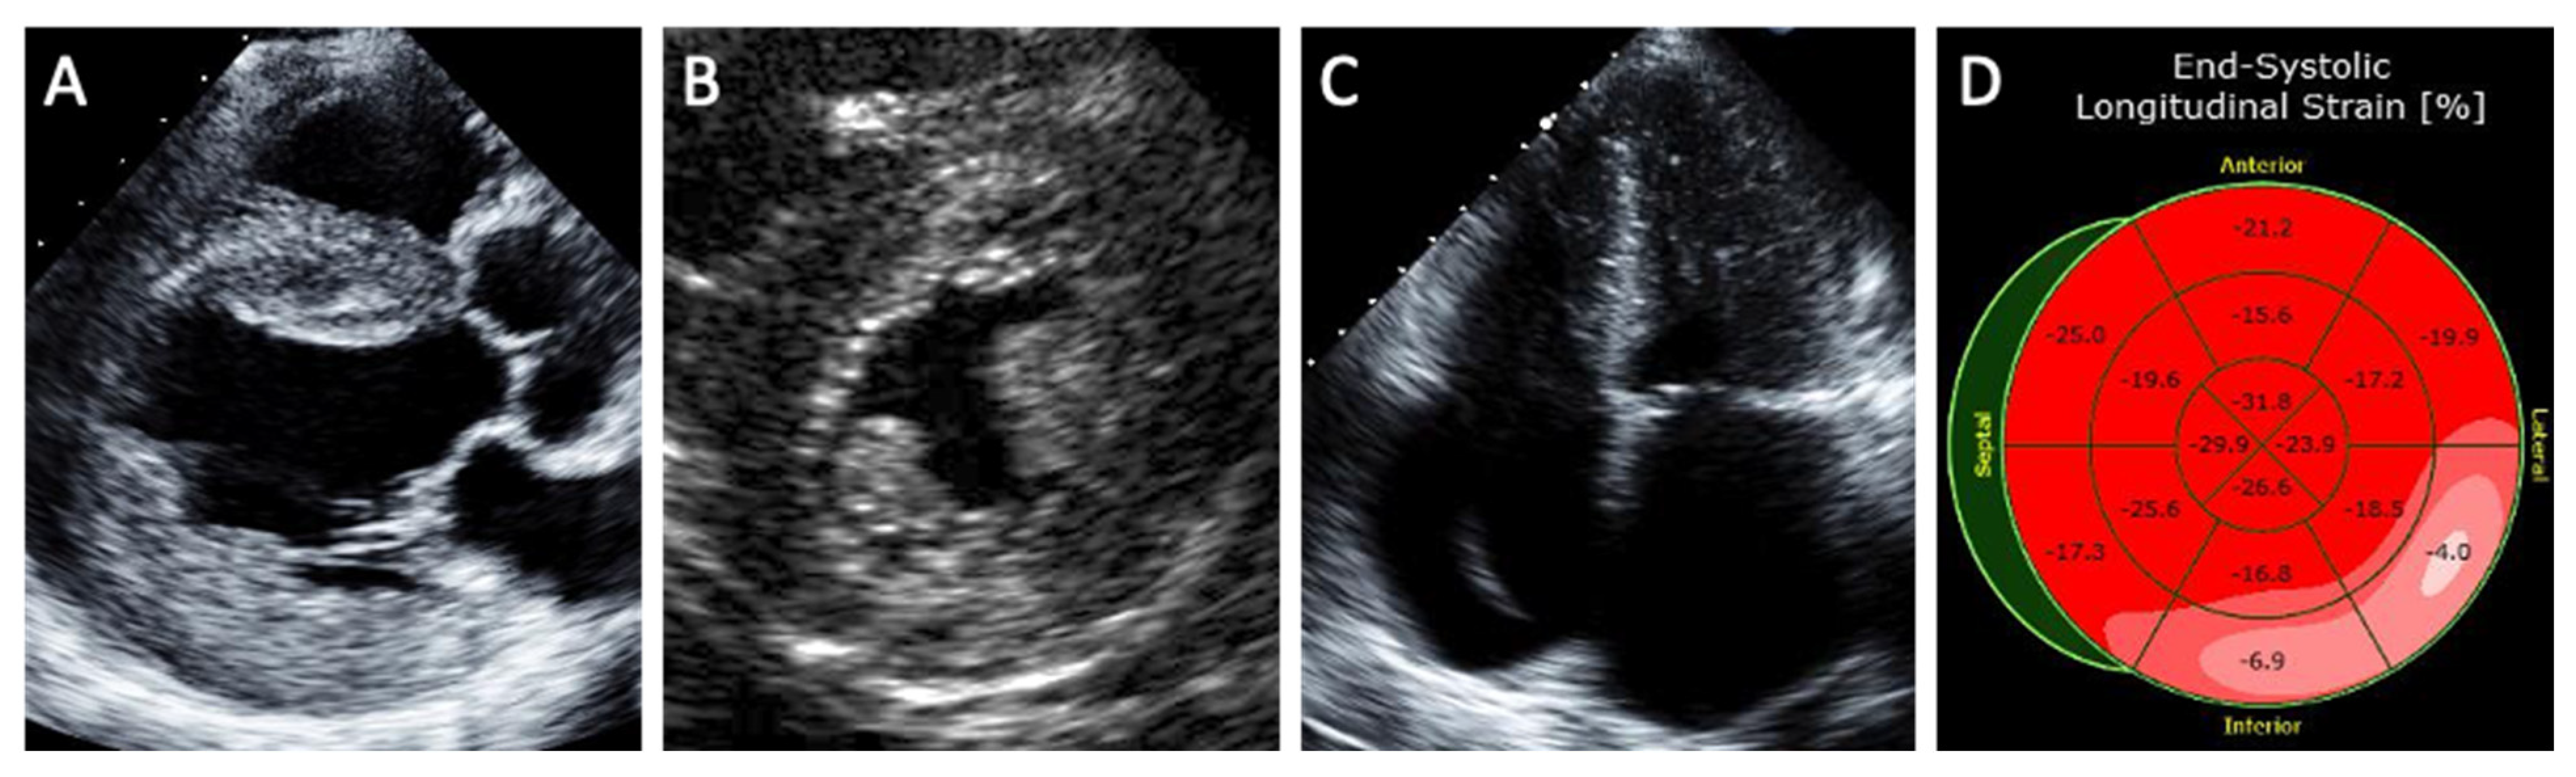

5.1. Echocardiography